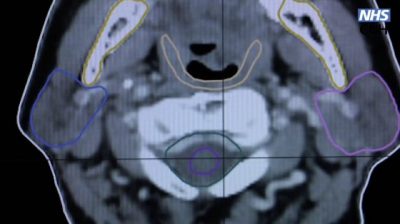

当患者需要进行放射治疗,事前要经过仪器扫描来识别肿瘤,以确定肿瘤位置和大小。然而,扫描过程非常耗时,医生要花费25分钟至2小时才能完成大约100个身体切面的扫描,以便能精准地绘制出骨骼和器官的轮廓,来确认放射的目标位置。这样才不会对周围的器官和正常细胞造成伤害。

为了迅速计算出放射线的投放位置,英国剑桥阿登布鲁克医院和微软一起合作开发了一个名“OSAIRIS”的AI系统。这套系统能够自动辨识和划出肿瘤的位置,缩短医生的诊断时间,能让患者尽快接受治疗。

在AI系统帮助下,整个扫描和绘制轮廓的速度提高了2.5倍,并且准确率高达90%。虽家减缓了工作量,但医生还是会亲自检查AI的绘制结果,确保细节无误才动手。然而,AI系统太过精准,根据英国广播公司(BBC)报道,有三分之二的情况下,医生没有做任何修改就直接采用AI所提供的结果。

最初,这项AI技术用来治疗前列腺癌和头颈癌。如今“OSAIRIS”显示有更大的潜能,可以帮助医生更早发现疾病,并为患者提供最好的康复机会。未来会应用在英国的医疗服务体系里面,涵盖其他癌症的类型。